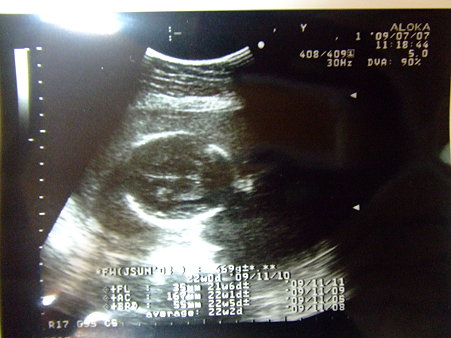

| 帰国後:初診:0707 尿検査・体重・採血・血圧測定 22w0d:469g |

DSCF0919 posted by (C)Katze |

FL:35mm AC:167mm BPD:55mm 今日も心臓バクバク動いてた 性別はまだ断定できないとの事 便秘気味 |